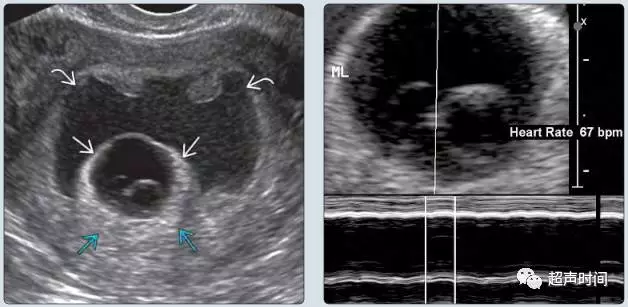

(1)观察是否有胎心活动。若活胎,测量胎心率,评估胎心率是否正常(< 90 次/分为心动过缓)。早孕期胎心率异常绝大多为心动过缓(图 3),但与血肿大小关系不大。约 80% 患者妊娠丢失。

图 3 妊娠囊(直箭头)外 2/3 以上区域为血肿环绕分布(弯曲箭头),测胎心率 67 次/分